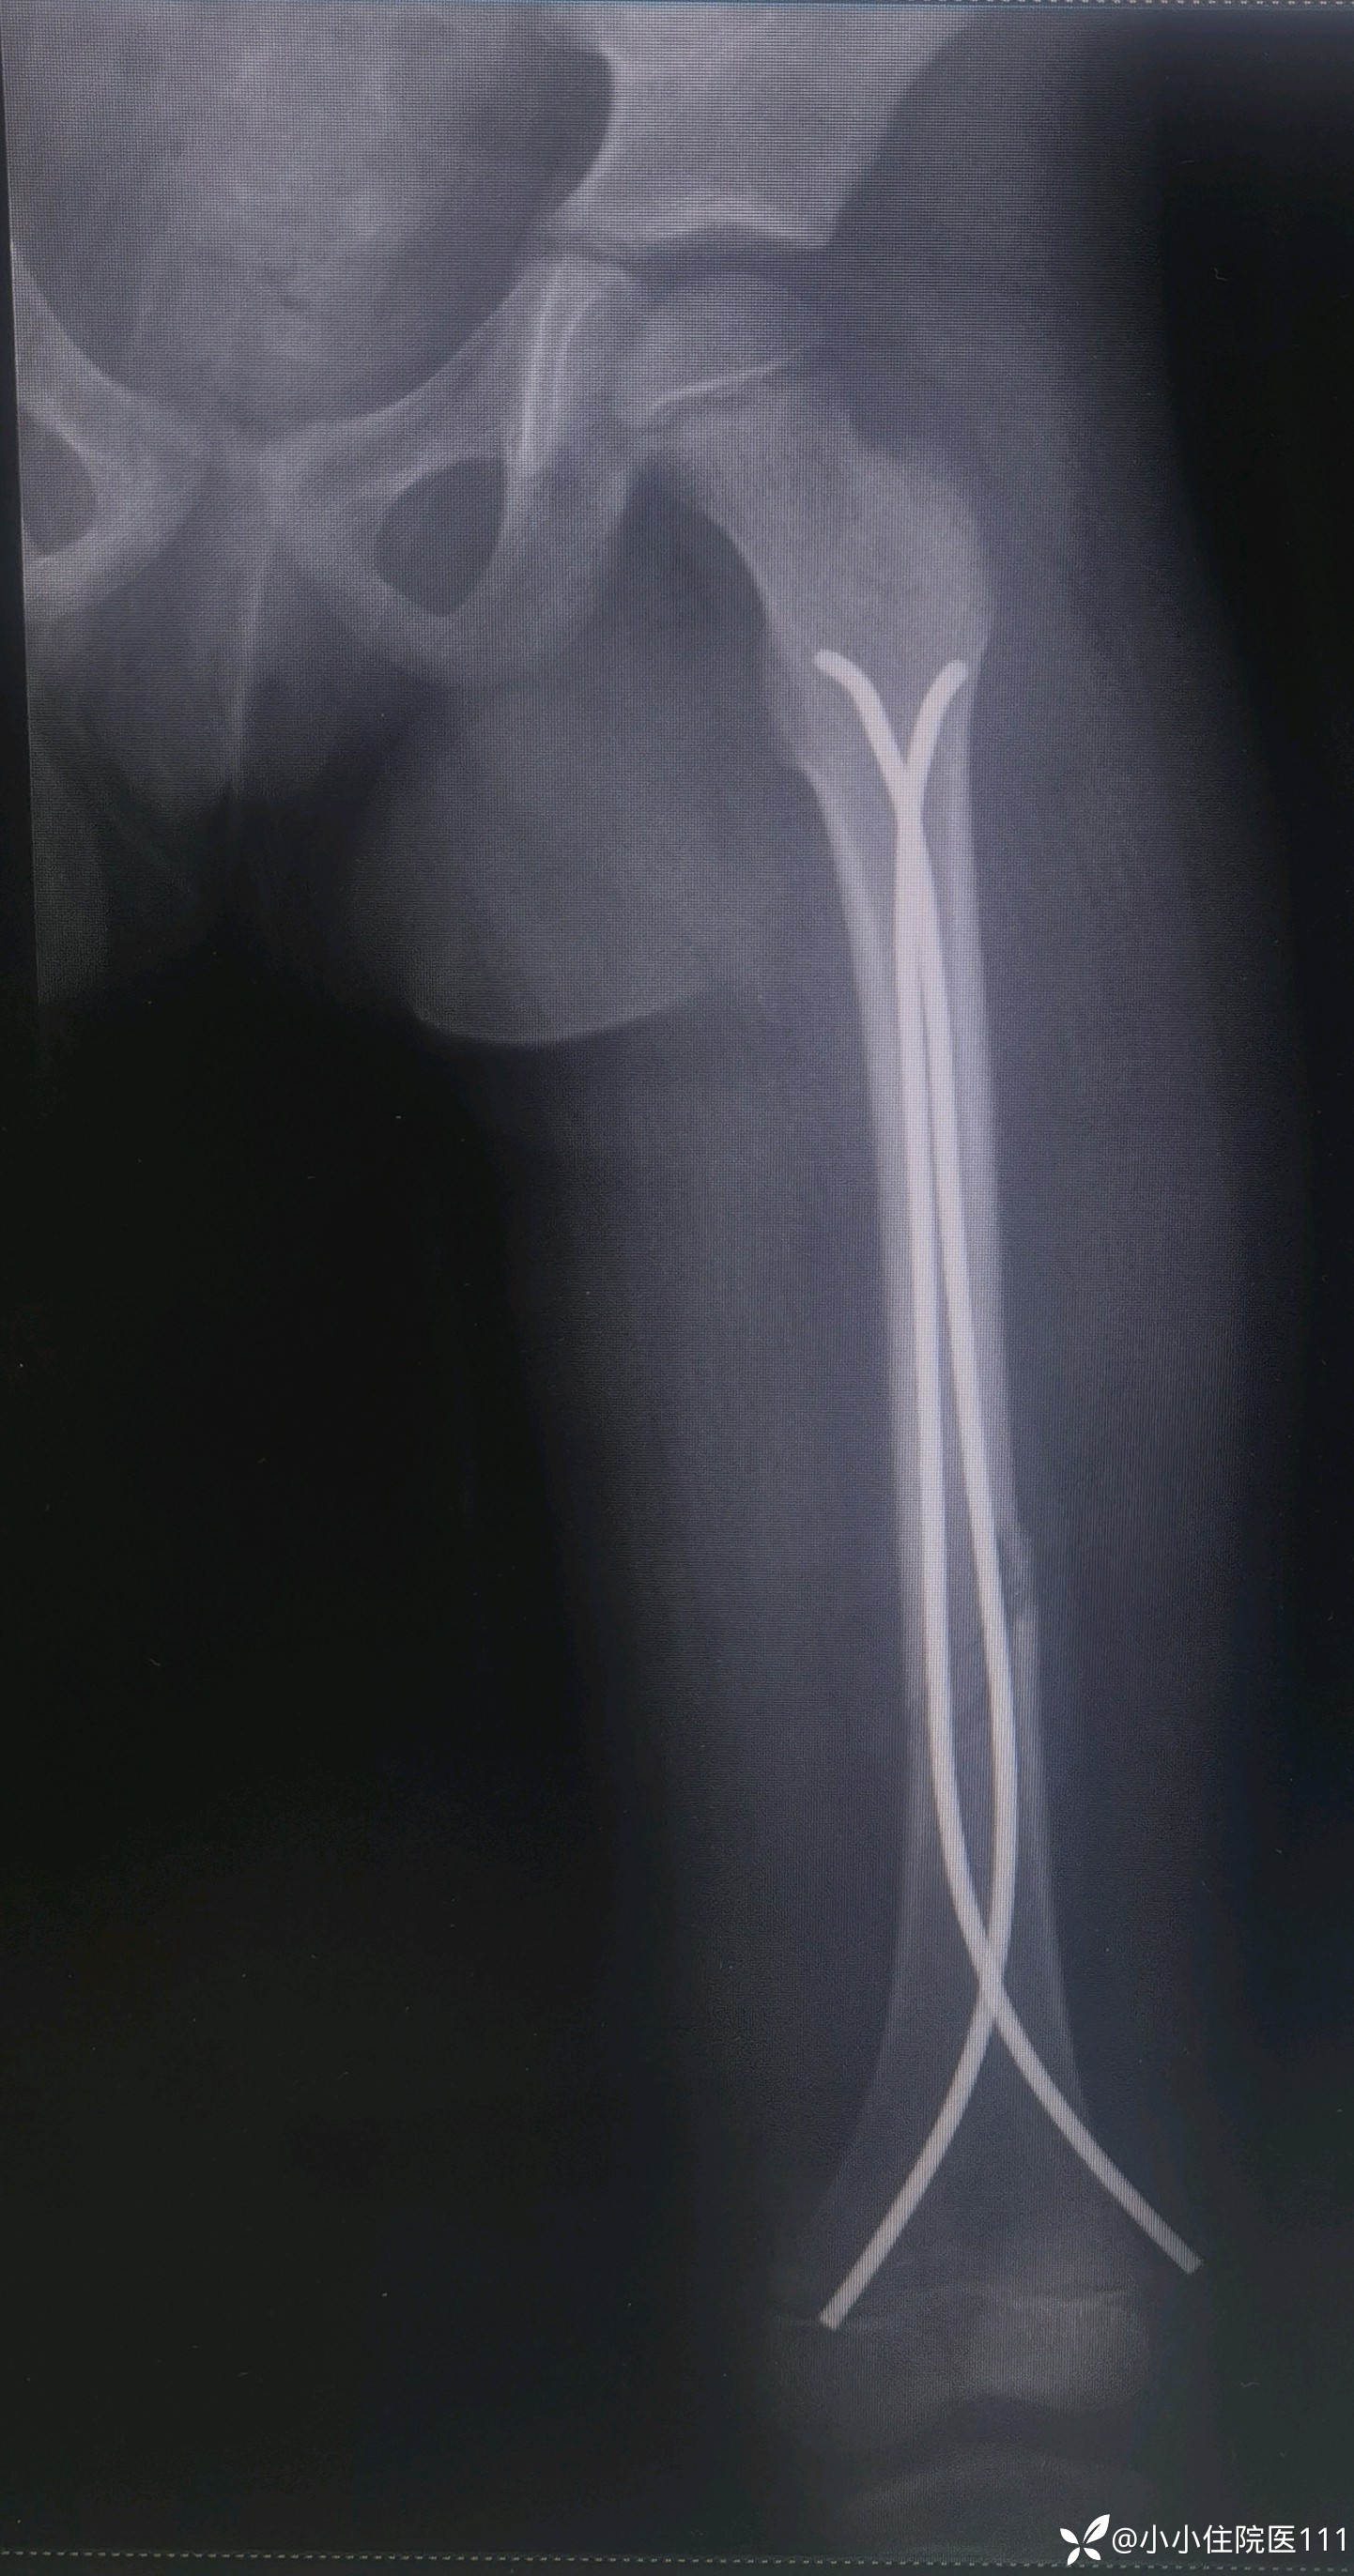

入院左股骨CT平扫及三维重建结果如下:

影像诊断:

左股骨中下段骨折,断端分高离、错位,部分重叠,伴周围软组织肿胀。

治疗经过:患儿入院后积极完善相关检查,排除手术禁忌症后,2023-05-25在手术室全麻下左侧额颞顶开放性颅脑损伤清创术+硬脑膜破裂修补术+颅骨凹陷骨折复位内固定术+头皮撕脱伤清创修复术+面部清创整形术+体表异物取出术;于2023-05-31在手术全麻下行左侧股骨干骨折切开复位弹性髓内钉内固定术、石膏固定术,治疗上予营养神经、抗感染、化痰、补液维持水电解质平衡、换药等对症处理。

(2023-06-09)复查左股骨正侧位片